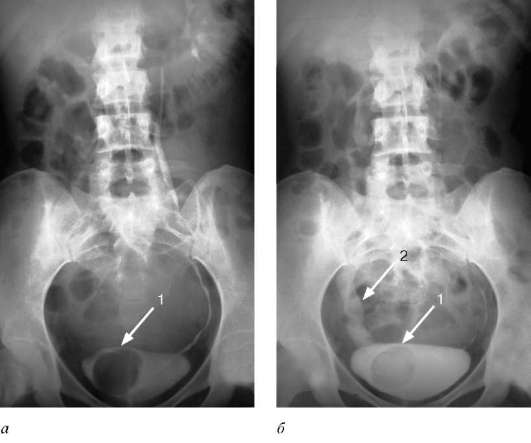

При дальнейшем обследовании, например, УЗИ мочевого пузыря, уролог обращает внимание на шарообразное выпячивание стенки: так диагностируется уретероцеле мочевого пузыря у женщин. С большой вероятностью при этом могут быть выявлены одно- или двухстороннее гидронефротическое видоизменение почек. Первичный диагноз подтверждает проведение рентгеноскопии: она однозначно показывает деформации мочевых каналов и проблемы с наполнением пузыря. Цистоскопия с вводом оптического датчика через мочеиспускательный канал позволяет детально обследовать устья, слизистые оболочки, определить размеры и форму уретероцеле.